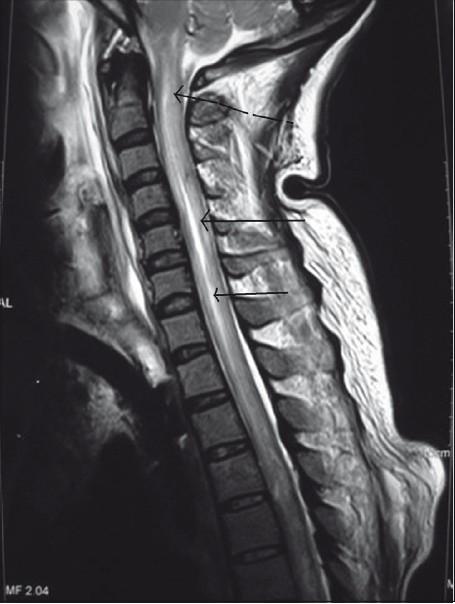

Delayed presentation of spinal cord trauma.

https://cdn.ncbi.nlm.nih.gov/pmc/blobs/4c72/3123003/da2b623f4ee9/JNRP-2-114-g001.jpg